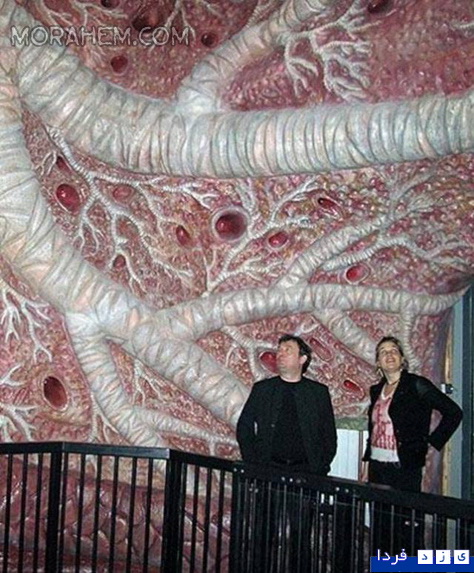

این ساختمان در هلند ساخته شده و با سفر به درون آن میتوان با بازدید از همه بخشها، از کارکرد درست یک بدن سالم آگاه شد و آموزش دید. ارتفاع این ساختمان که از نظر ظاهری پیکر انسانی نشسته است، 35 متر است.

این تصاویر عجیب و بی نظیری كه مشاهده می کنید مربوط به یك ساختمان واقع در كشور هلند است كه شبیه انسان ساخته شده و از تاریخ چهاردهم مارس 2008 برای بازدیدكنندگان فعال بوده است. بطوریکه با سفر به درون آن میتوان از تمامی قسمت ها و کارکرد درست یک بدن انسان سالم اطلاعات لازم را کسب کرد و در این تجربه جدید برای بازدیدكنندگان خصوصا دانشجویان رشته پزشکی این امکان فراهم شده بود تا با قسمتهای داخلی بدن انسان و نحوه فعالیتهای آنها از نزدیك آشنا شوند.

این بنای انسانی که از نظر ظاهری پیکر انسانی نشسته است، در كنار یك ساختمان شیشه ای با ارتفاع 35 متر بنا شده كه در جوار اتوبان A44 آمستردام به هاگو (Hague) قابل مشاهده است. گرچه این تصاویر شاید برای شما دوستان پرشین استار چندان جدید نباشد ولی آنچه مهم است اهمیت آموزش و ایجاد انگیزه برای سهولت در شناخت و درک بهتر ساختمان پیچیده و اسرار آمیز بدن انسان نسبت به نیاز محققین و دانش اندوزانی است که مایلند به گوشه ای از اسرار عظمت خلقت خداوند که همان اشرف مخلوقات است دست یابند.